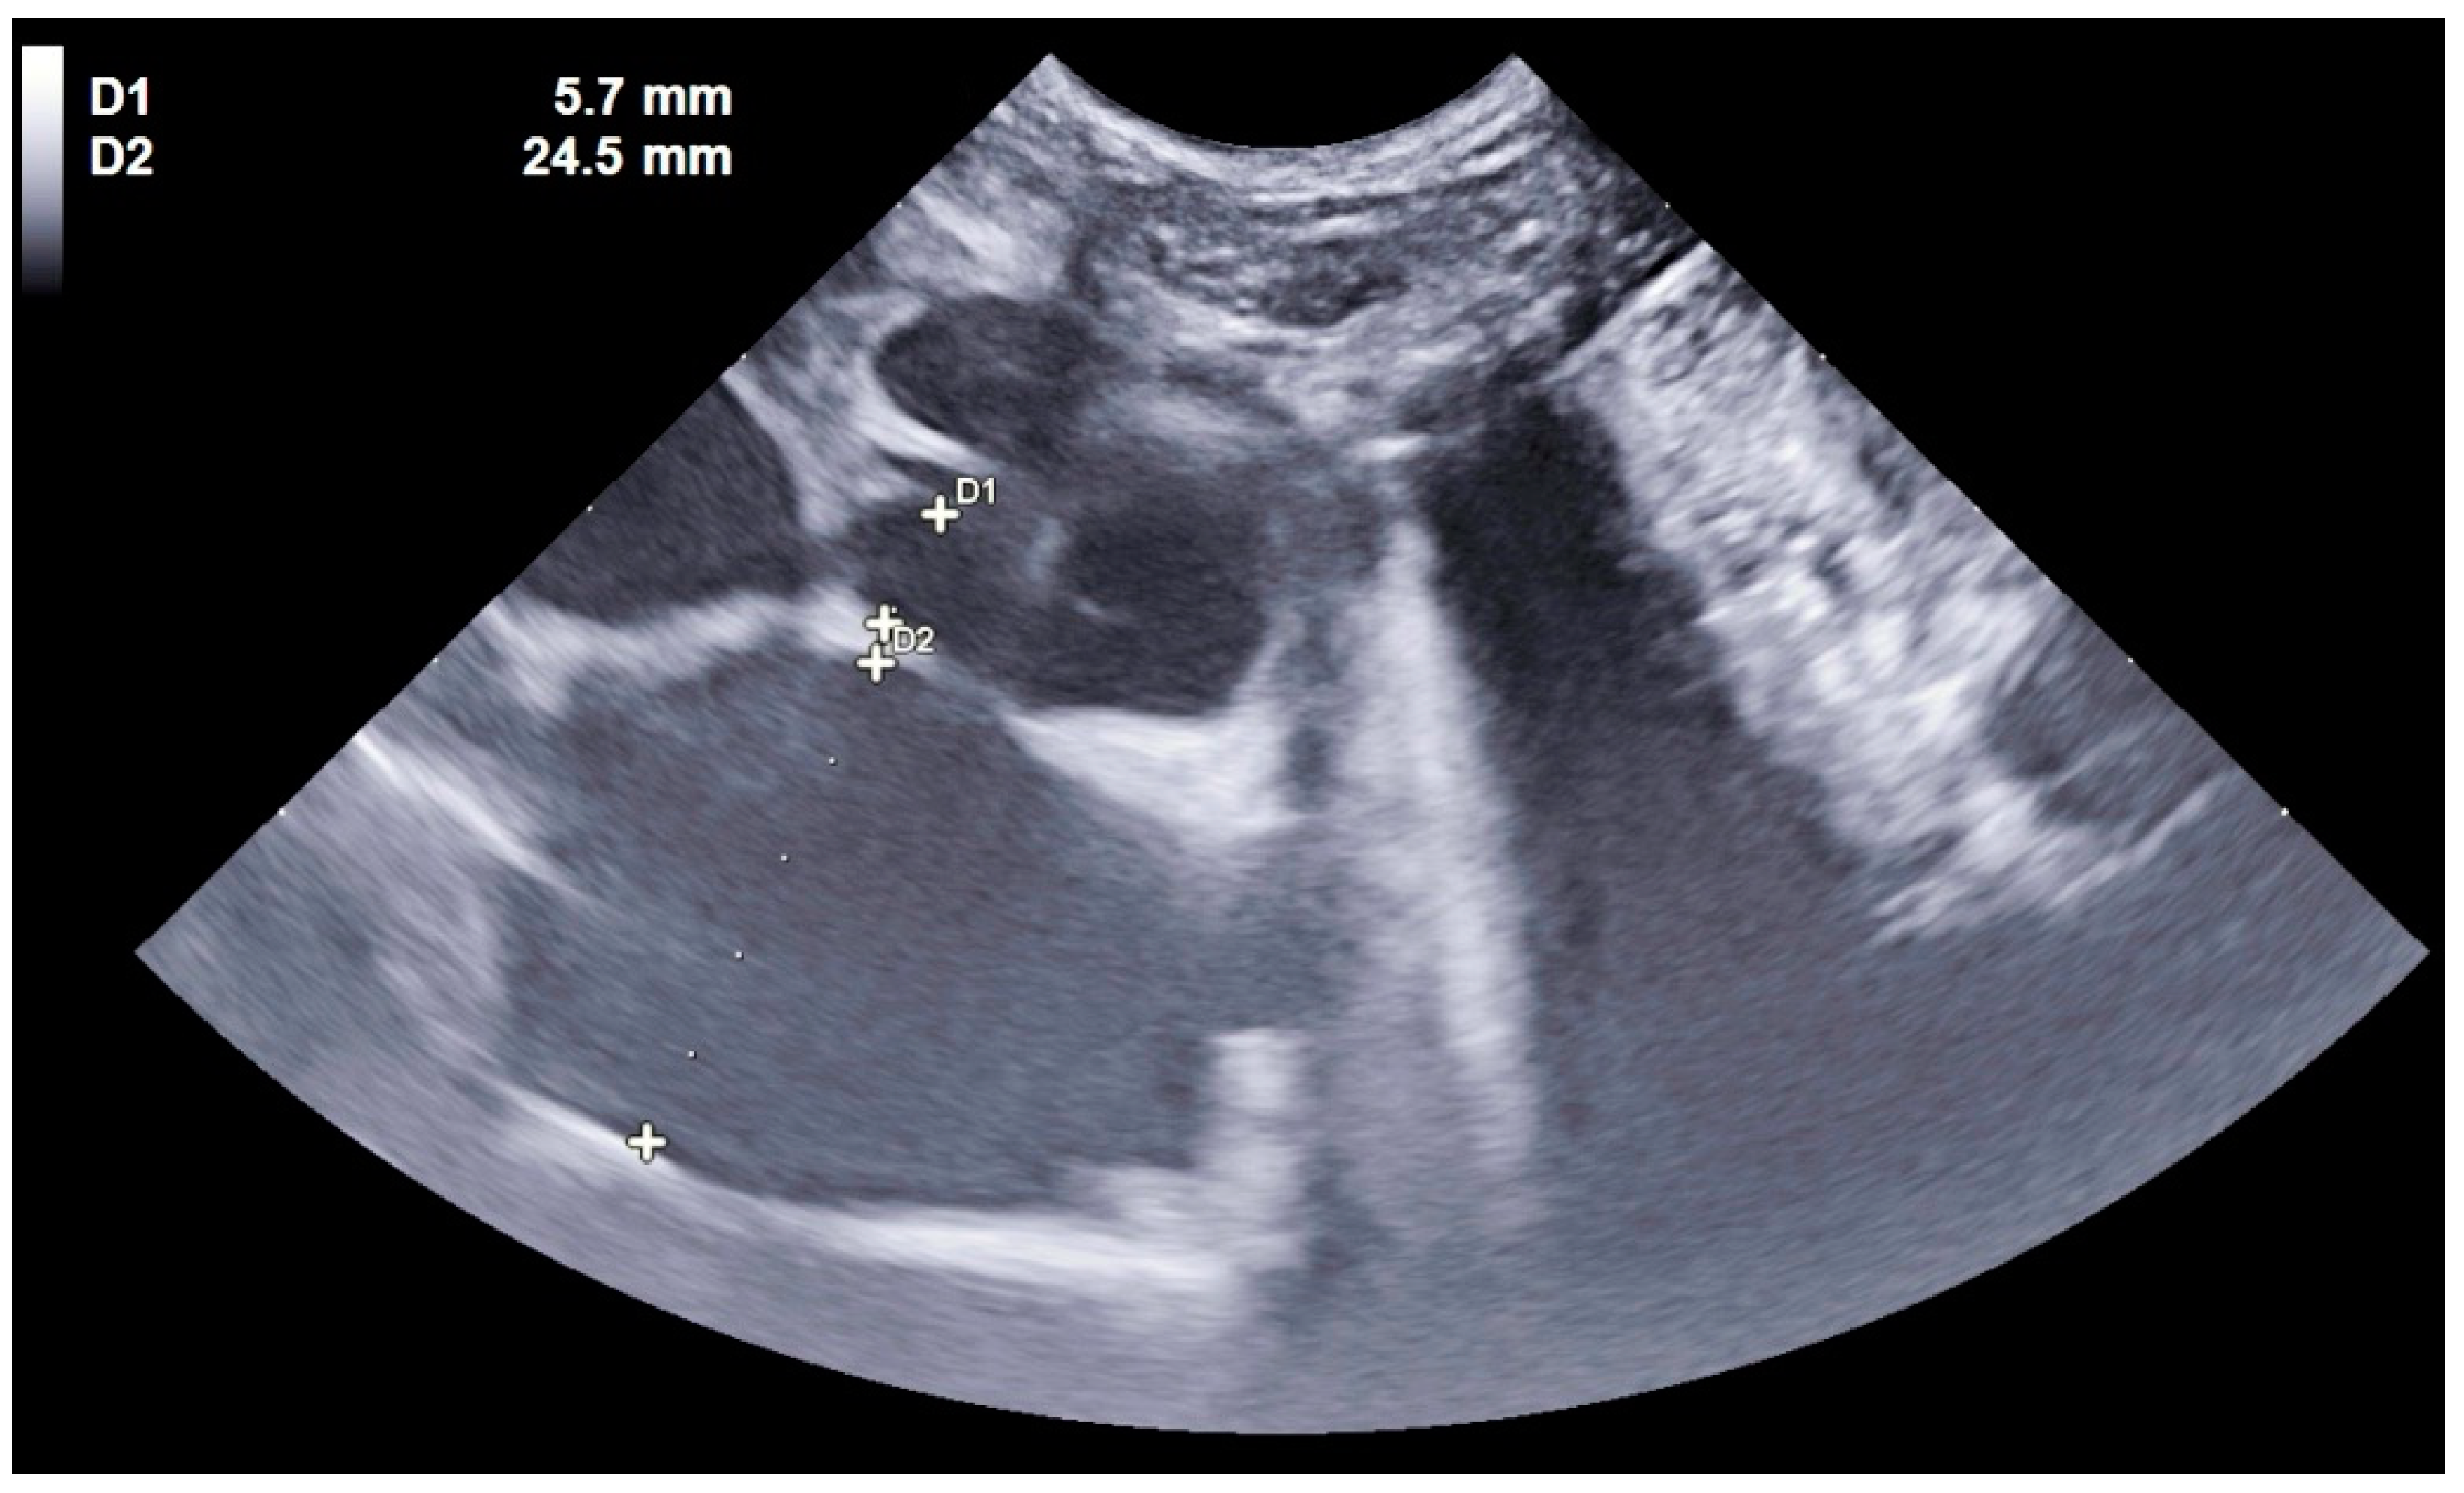

- Pleural effusions